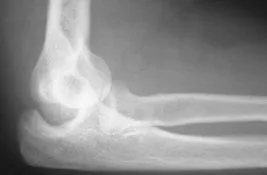

A complex dislocation of the elbow. In addition to dislocation, there are multiple fractures of the elbow.

In a complex elbow dislocation, surgery may be necessary to restore bone alignment and repair ligaments. It can be difficult to realign a complex elbow dislocation and to keep the joint in line.

After surgery, the elbow may be protected with an external hinge. This device protects the elbow from dislocating again. If blood vessel or nerve injuries are associated with the elbow dislocation, additional surgery may be needed to repair the blood vessels and nerves and repair bone and ligament injuries.